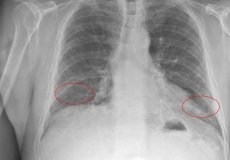

Двусторонняя пневмония у ребенка — опасная форма пневмонии, поражающая обе стороны легких, в отличие от односторонней пневмонии. Он может иметь бактериальную или вирусную природу. В нашей статье мы обсудим, что такое односторонняя и двусторонняя пневмония (ее еще называют двусторонней), симптомы, методы диагностики и лечения. Что это такое? Это инфекционно-воспалительный процесс в тканях легких, вызываемый атакой …